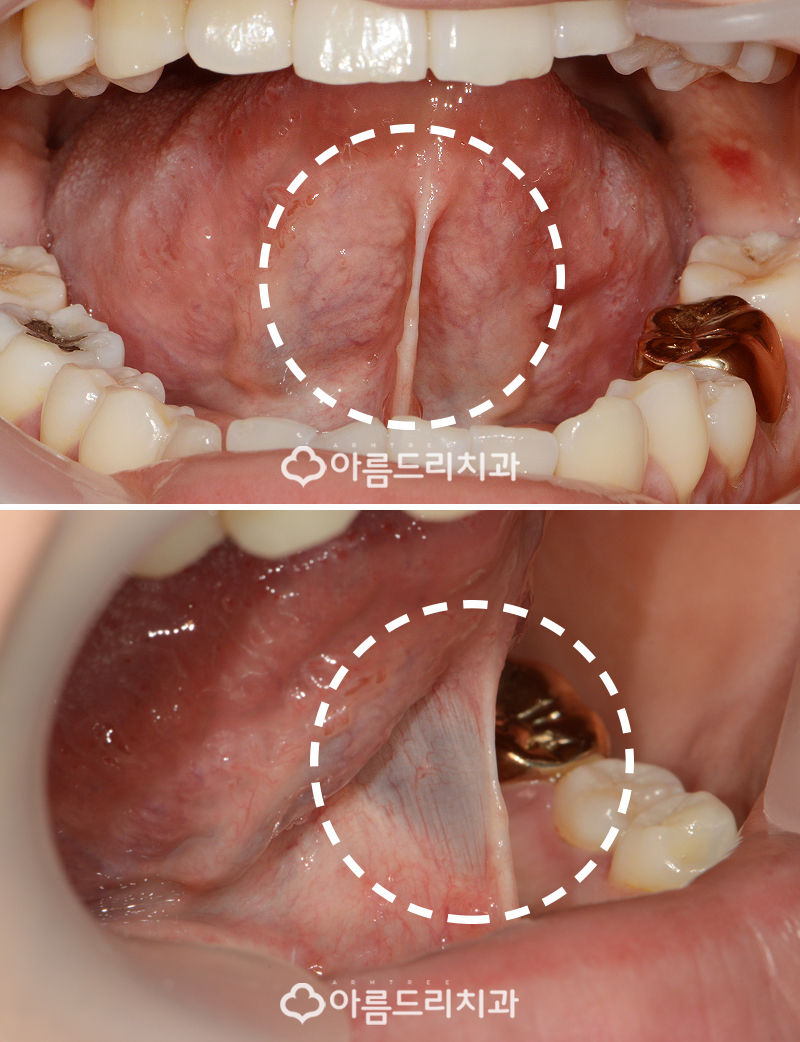

자~ 그렇다면 환자분의 설소대 그 상태가 어떤지 성인 설소대수술 전 사진을 볼까요?

무언가 일반인들과 다른부분을 느끼셨나요? 아래에서 다시한번 설명을 드리겠지만, 제가 동그란 점선으로 표시를 해놓은 부분이 바로 설소대인데 다른사람들에 비해 매우 짧았어요.

사진을 보고 어떠한 부분이 설소대인지 헷갈리 시는 분들을 위해서 혀의 구조에 대해 한번 더 설명해드리고 넘어가는게 좋을 것 같습니다.

설소대는 입안의 바닥면과 혀의 아래에 있는 면을 연결하는 막인데 이것이 짧으면 당연히 혀가 운동할 수 있는 범위가 제한되게 됩니다.

환자분의 경우 이전에 수술을 했던 환자분들 보다도 더 짧은 설소대를 가지고 계셨으며 혀를 내밀은 모습을 정면에서 보면 조금만 혀를 내밀어도 혀 끝이 땡겨져 'W'모양이 나타날 정도로 설소대 자체가 매우 짧았으며 발음에 장애가 있었을 것이 느껴졌습니다.